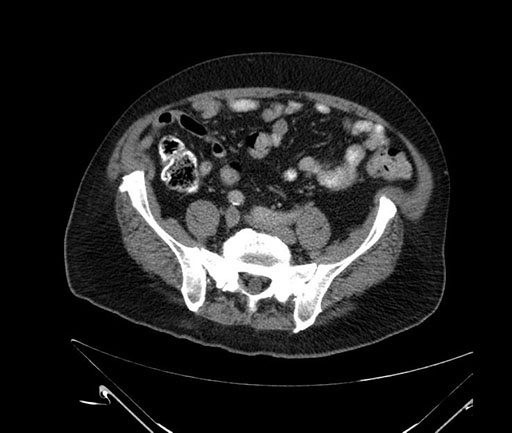

Imaging Analysis

Look through the patient's CT scan to identify any areas of concern for the necessary procedure.

Based on your CT findings, which issue(s) would give reason for "planned slowing down moment(s)" in this case?